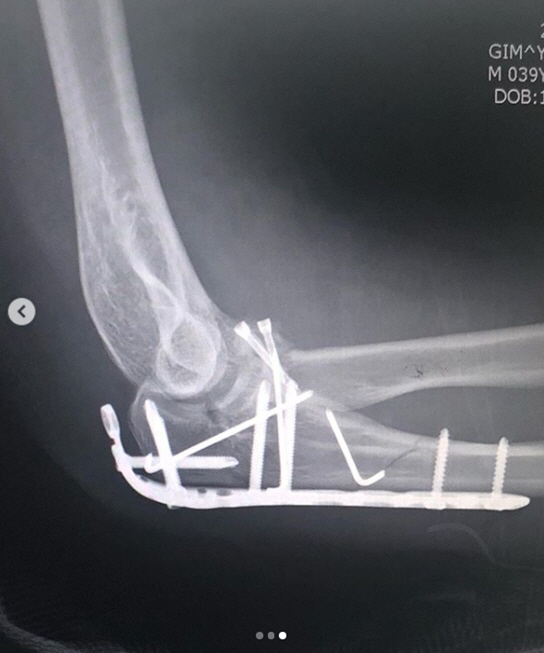

개코는 29일 자신의 인스타그램에 "뜻하지 않게 로봇팔이 되어 버렸네요. 좋으신 의료진 분들 덕에 수술은 잘 되었습니다"라는 글과 함께 사진을 게재했다.

공개된 사진 속 개코는 병원 침대 위에 누워 부상당한 오른쪽 팔에 붕대를 감고 망연자실한 표정으로 카메라를 응시하고 있다. 또한 개코는 팔에 철심을 박은 엑스레이 사진도 공개해 안타까움을 자아냈다.